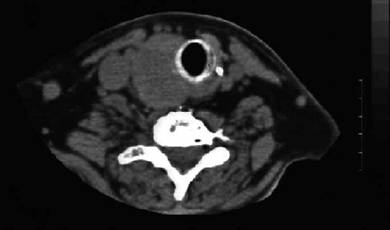

Scintigrafia si CT aceluiasi pacient, metastaza laterocervicala stg ce impinge traheea spre dr.

Femeie de 70 ani. Disfonie progresiva prin

paralizie de recurent drept. Nodul voluminos (35 x 25 x 43 mm, 19 cc) care ocupa

aproape complet lobul drept, neomogen, hipoecogen, cu arie anterioara

hipoecogena. Lob stang nevizuzlizat (probabil agenezie). Calcitonina =

820 pg/ml. (v.n. <10pg)

CEA= 638 ng/ml (v.n. <8 ng).

Examen citologic prin citoaspiratie: carcinom midolar cu celule spindle.

CT – aceeasi pacienta – agenezie lob stang